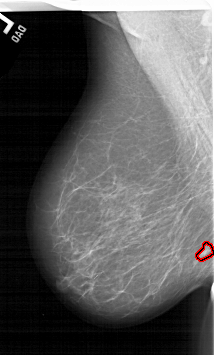

A_1464_1.LEFT_MLO

LEFT_MLO LINES 6031 PIXELS_PER_LINE 3631 BITS_PER_PIXEL 12 RESOLUTION 43.5 OVERLAY

FILE: A_1464_1.LEFT_MLO.OVERLAY

TOTAL_ABNORMALITIES 1

ABNORMALITY 1

LESION_TYPE MASS SHAPE IRREGULAR MARGINS ILL_DEFINED

ASSESSMENT 4

SUBTLETY 2

PATHOLOGY MALIGNANT

TOTAL_OUTLINES 1

BOUNDARY